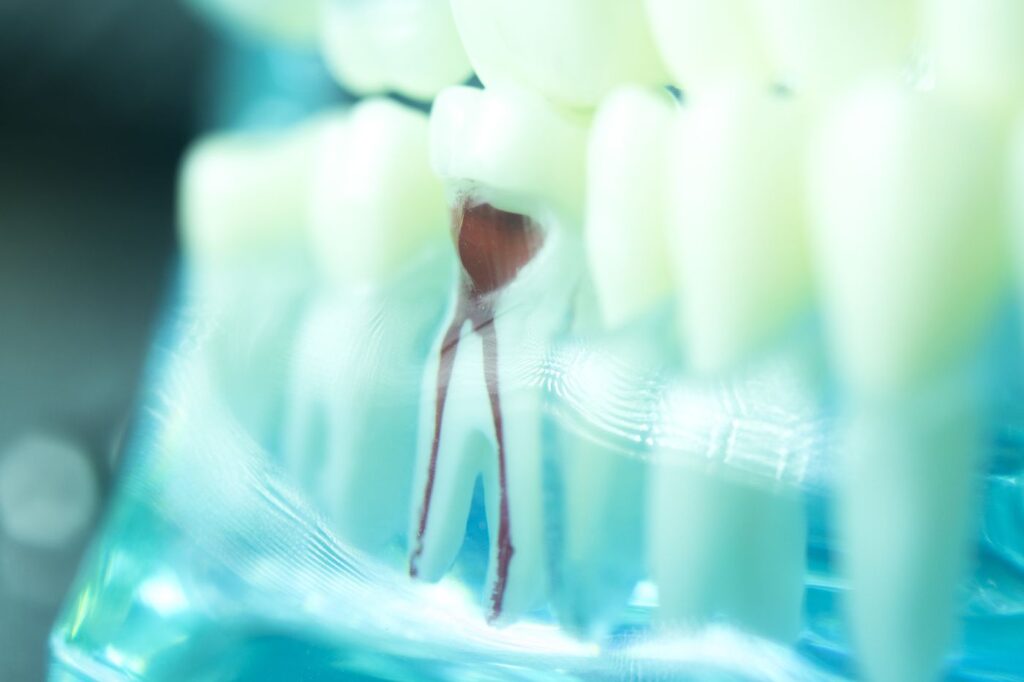

Root canal therapy is a common dental procedure performed by Dr. Valdes at Vibrant Dental in Hendersonville, NC. This treatment is designed to repair and save a severely damaged or infected tooth, rather than extracting it. Root canal therapy involves removing the infected or inflamed pulp from inside the tooth, carefully cleaning and disinfecting the root canal, and then filling and sealing it to prevent further infection. This highly effective treatment can relieve toothache, stop infection, and preserve your natural tooth, allowing you to maintain your normal biting force and sensation, and keep your smile beautiful.

Examination and

X-ray

First, Dr. Valdes will thoroughly examine your tooth and take an X-ray to assess the extent of the damage and infection. This step is crucial for planning the treatment and ensuring the best possible outcome.

Anesthesia and

Pulp Removal

Before the procedure begins, local anesthesia is administered to numb the area and ensure your comfort throughout the procedure. Then, Dr. Valdes will make a small opening in the crown of your tooth to access the pulp chamber. The infected or inflamed pulp is then carefully removed.

Cleaning, Filling, and Sealing

After the pulp has been removed, the inside of your tooth will be thoroughly cleaned and disinfected. Then, the root canal will be filled with a biocompatible material and sealed with a temporary filling. A crown will be placed at a later visit to protect the tooth and restore its function.